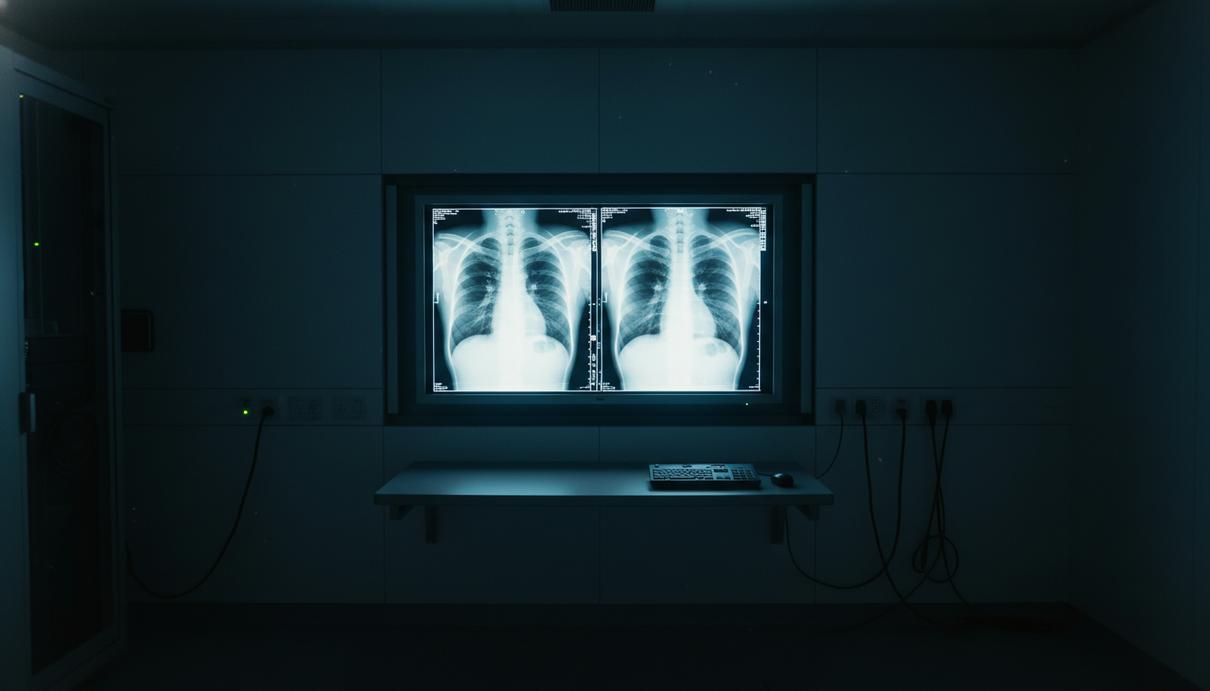

Медицинский монитор с двумя сравнительными рентгеновскими снимками грудной клетки в темном кабинете.

Исследование, опубликованное в журнале Radiology, показало, что опытные рентгенологи и современные мультимодальные языковые модели испытывают серьезные трудности с идентификацией медицинских изображений, созданных при помощи искусственного интеллекта. Специалисты не всегда могут отличить подлинные рентгенограммы от глубоких фейков, что ставит под угрозу безопасность цифровых архивов и достоверность диагностики.